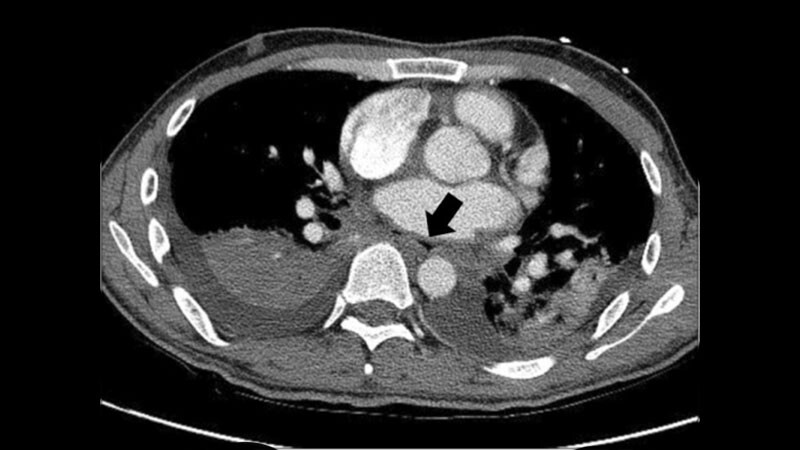

Pulsed Field Ablation Treats AF With Few ComplicationsNew-technology pulsed field ablation successfully isolated pulmonary veins with mini-mal complications to treat paroxysmal

and persistent atrial fibrillation, a retrospective study has shown.